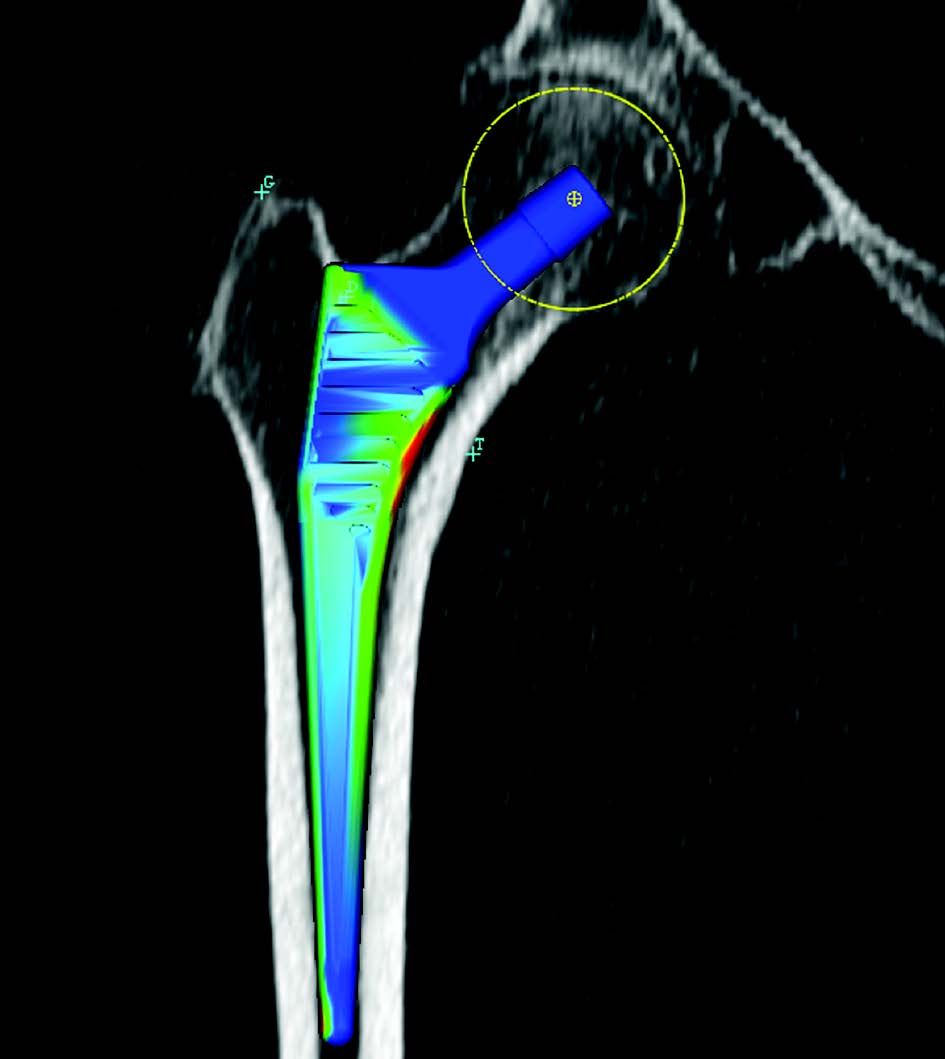

Step 6: femoral stem planning: we can position a stem, choose the size, evaluate bone stress, measure bone resection (that we can compare during surgery using the callipers) and choose the ball (Fig. 6 and 7). The software calculates lengthening and offset depending on the implants selected.

Concordance between the size of the stem planned on a layer and the size of the stem implanted is sometimes lower than 50 % using standard x-rays. This is also due to several factors: x-ray magnification error, femur in external rotation which reduces the diameter of the duct and under evaluates the offset.

Under evaluation of the offset is the main disadvantage of standard x-ray (Fig. 8). Under evaluation can reach 1 cm with x-ray planning. The risk is thus doubled: risk of prosthetic medialisation and risk of prosthetic instability. The instability observed during surgery may mislead the surgeon who will proceed with lengthening, either by using a larger sized stem or a longer ball. Offset quantification has been discussed in several publications: Medialisation carries the risk of instability and excessive lateralisation and pain. Boddu described an index for the lesser trochanter to predict under evaluation. Merle recommended taking a frontal hip x-ray in addition to the pelvic x-ray (13).

Concordance between planned and implanted stems is higher than 90 % with the CT-scan (100 % for Edi Sariali with an anatomical stem, 100 % pour Hassani (19) and 92 % in a personal prospective series of 100 records with straight stem).